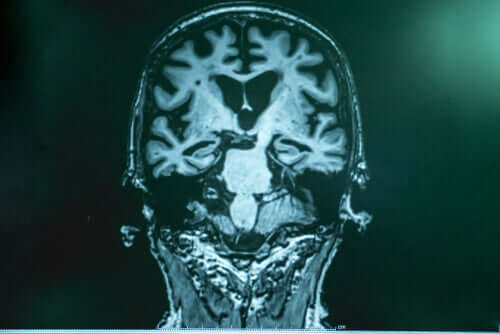

Il Dottor Lopera spiega che in caso di Alzheimer si verifica una sorta di accumulo di “spazzatura” nel cervello. Quest’ultima è composta da una proteina chiamata amiloide. I frammenti della stessa si uniscono e formano una “colla” che aderisce ai neuroni, causando una raffica di errori. L’altra parte della spazzatura è costituita dalla proteina tau, che avvolge il neurone, lo rinchiude e lo uccide. La Tau è la parte più nociva.